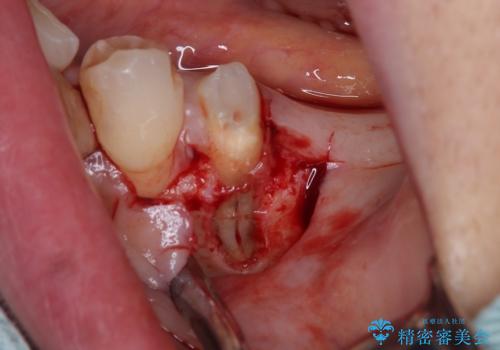

左下小臼歯は根管治療で対応する予定でしたが、診断のために歯肉を開いたところ頬側に垂直破折が認められたため、抜歯即時埋入インプラントによる補綴治療を選択することとしました。

インプラント埋入時に十分な安定値を得ることができたため、速やかに仮歯を装着し、最小限の通院回数で治療を終えることができました。